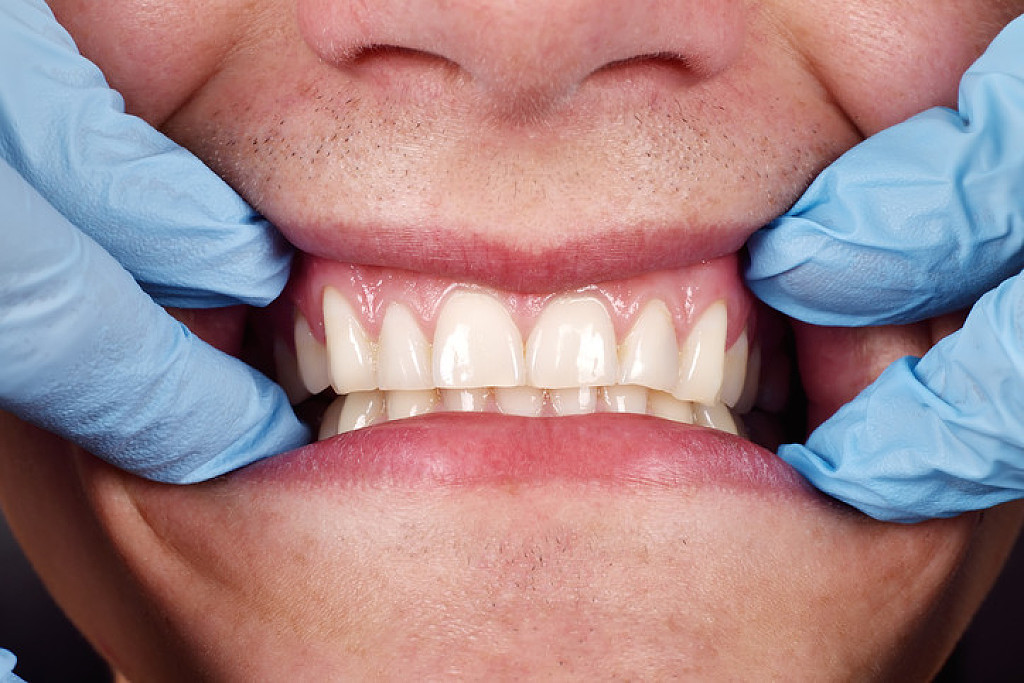

Gingival hyperplasia is an enlargement or overgrowth of the gum tissue, also known as the gingiva, around the necks of the teeth. It is an increase in the size of the gingival tissues and thus the term overgrowth is many times used in place of the term hyperplasia.

Gingival overgrowth can be caused by several mechanisms but will have very similar appearances. A study in the journal Histopathology describes the condition as "a small papillary or velvety bright red gingival overgrowth that bleeds easily." However, the overgrowth can be extensive and round in appearance. It is usually found on the front of the teeth and can be on the tongue side in some cases.